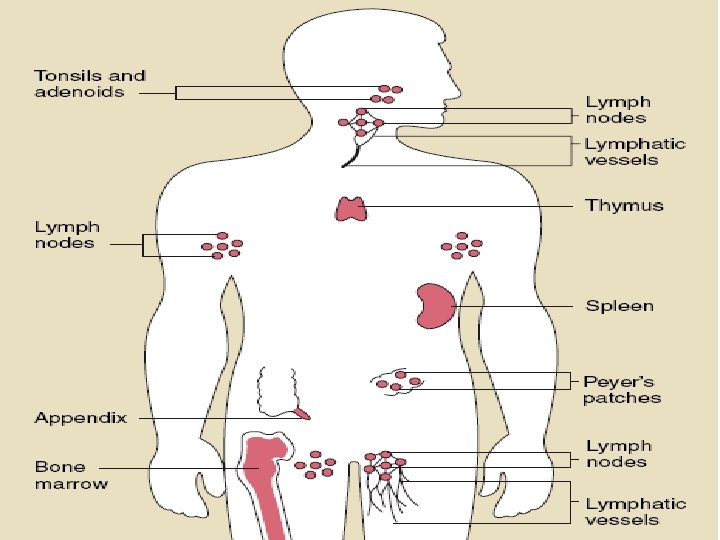

The major components of the immune system are: • Immunocompetent cells • Antibodies • Complement system • Bone marrow • Thymus • Spleen • Lymph nodes • Tonsils